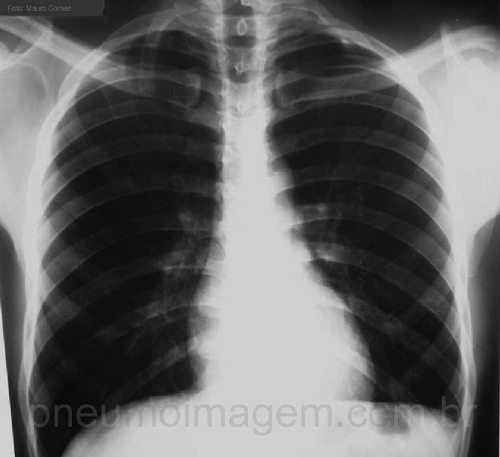

CASO CLÍNICO #5Paciente do sexo masculino que apresenta-se com dor intermitente e relacionada aos movimentos no membro superior direito, parestesia e diminuição de força muscular. Olhe atentamente a sua radiografia de tórax e deixe os seus comentários abaixo.

Male patient with intermittent pain and related to movements in the right arm and paresthesia with decreased muscle strength. Look closely at your chest radiography and leave your comments below.

costelas cervicais direita e esquerda, agenesia do 1º arco costal e.

O paciente apresenta costela cervical a direita